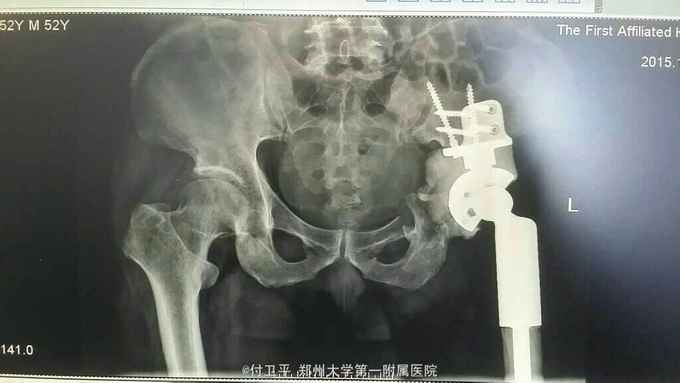

患者双下肢血栓形成,请血管外科会诊后,行“下腔静脉造影并滤器植入术”,并指导正规抗凝治疗,完善相关术前准备后,择期局麻下行“左股骨头病变穿刺活检术”,术中取中心及边缘病变组织各一份,术后病理回示:考虑透明细胞软骨肉瘤,经我院骨肿瘤学组及北京会诊后,确诊为:透明细胞软骨肉瘤,因肿瘤波及到髋臼,制定手术方案:左侧半骨盆置换术,与家属沟通后,定制假体,择期行“左髋臼及股骨头透明软骨肉瘤切除+人工半骨盆置换术”,术中取右侧卧位漂浮体位,肿瘤广泛性切除,术中出血约1300ml,术顺。

透明细胞软骨肉瘤为罕见的骨恶性肿瘤,约占所有软骨肉瘤的百分之一,属于一种低度恶性肿瘤,好发于长骨干骺端,多见于成年男性,高峰年龄30-50岁,该瘤需与“软骨母细胞瘤”、“骨肉瘤”及“转移性透明细胞癌”鉴别,特点:生长缓慢,易复发,极少转移,一般术后不常规放化疗等辅助治疗,目前多采用病变区骨与软组织广泛切除,预后良好。